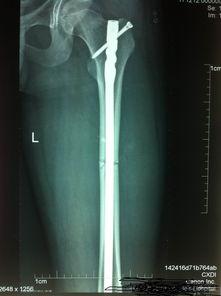

在手术前,医生会对患者进行详细的检查,确保手术的顺利进行。他们会为患者进行X光检查,了解股骨骨折的具体情况。此外,医生还会对患者进行血液检查,以确保患者没有手术禁忌症。

手术开始,医生首先会使用一种叫做“导针”的工具,在患者的股骨上找到合适的插入点。导针的作用是引导股骨髓内钉进入正确的位置。接下来,医生会使用一种叫做“钻头”的工具,在导针的引导下,在股骨内部钻出一个通道。

当通道钻好后,医生会将股骨髓内钉插入通道中。在这个过程中,C型臂会不断调整角度,确保钉子插入的位置准确无误。钉子插入后,医生会使用一种叫做“扳手”的工具,将钉子固定在股骨上。